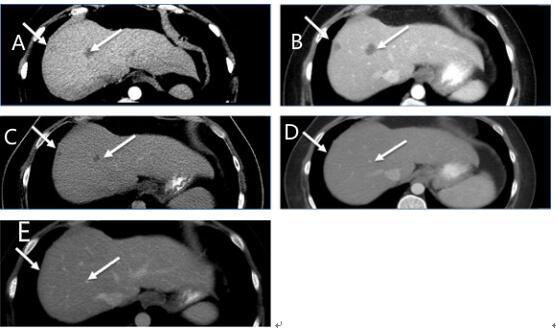

患者出现发热和寒战,并发生皮疹,但是当dabrafenib剂量降低至75 mg / d后,病人迅速改善。 治疗1个月后CT扫描,具有显著的影像学变化,纵隔淋巴结肿大缩小,没有新的肝或纵隔病变(图1A和B和2A和B与图1C和2C),并且在3个月时的影像学检查显示出纵隔淋巴结肿大和肝脏局部病变进一步缓解(图1D和2D)。 8个月的影像显示纵隔淋巴结持续缩小,肝脏病变完全消退(图1E和2E)。 患者目前仍继续进行治疗。

图2:ABCDE